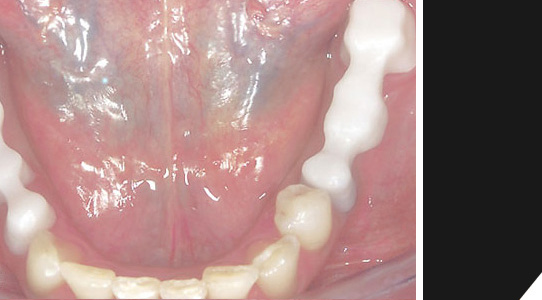

In der Präsentation sehen Sie einen

Patienten mit:

1. Goldkronen

2. Kronen entfernt und unverblendete Zirkonbrücke

3. Fertig, Brücke verblendet